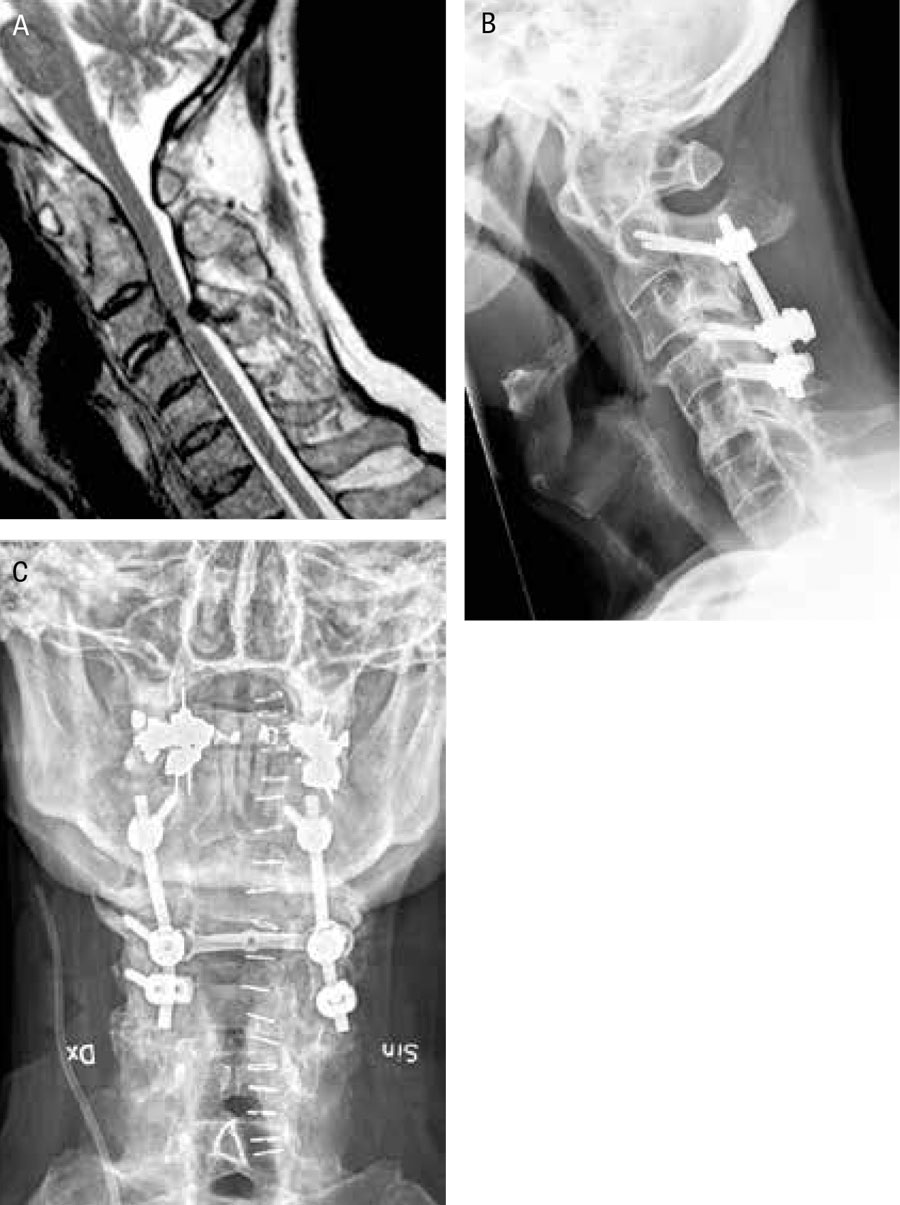

A) MRT-bild med T2-sekvens i sagittalplan av cervikalryggen hos patient med ankolyserande spondylit. På grund av endast en kvarvarande rörlig cervikalryggsnivå (C 3–C 4) har spinal stenos utvecklats med ryggmärgspåverkan som följd. B) och C) postoperativa bilder (sagittalprojektion respektive anterioposterior projektion) efter bakre kirurgi med dekompression och instrumenterad fusion.